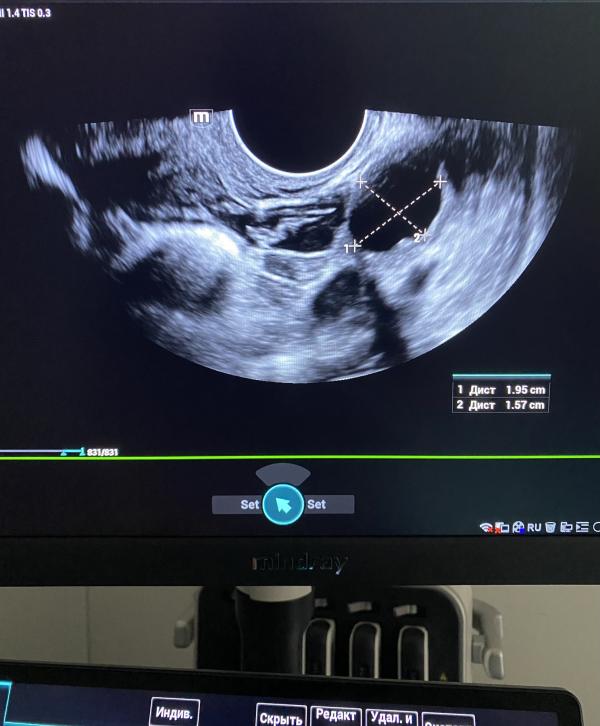

Послеродовой осмотр: когда идти, что делают, как проходит без боли? Консультация, кольпоскопия, мазки, УЗИ

Плановый послеродовой осмотр.

Без боли и страхов.

Консультация, кольпоскопия,

взятие мазков,

узи исследование.